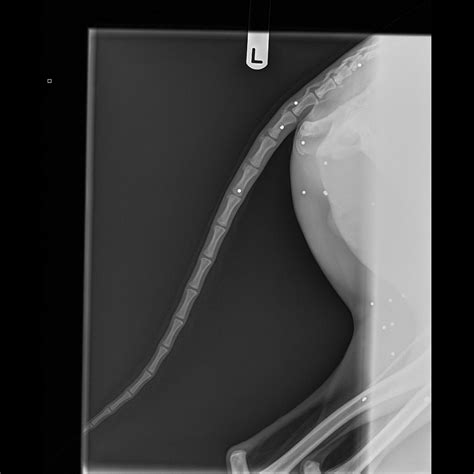

• X-Rays or Imaging: Imaging tests may be ordered to assess the extent of internal damage, especially if the BB is still lodged in the body.